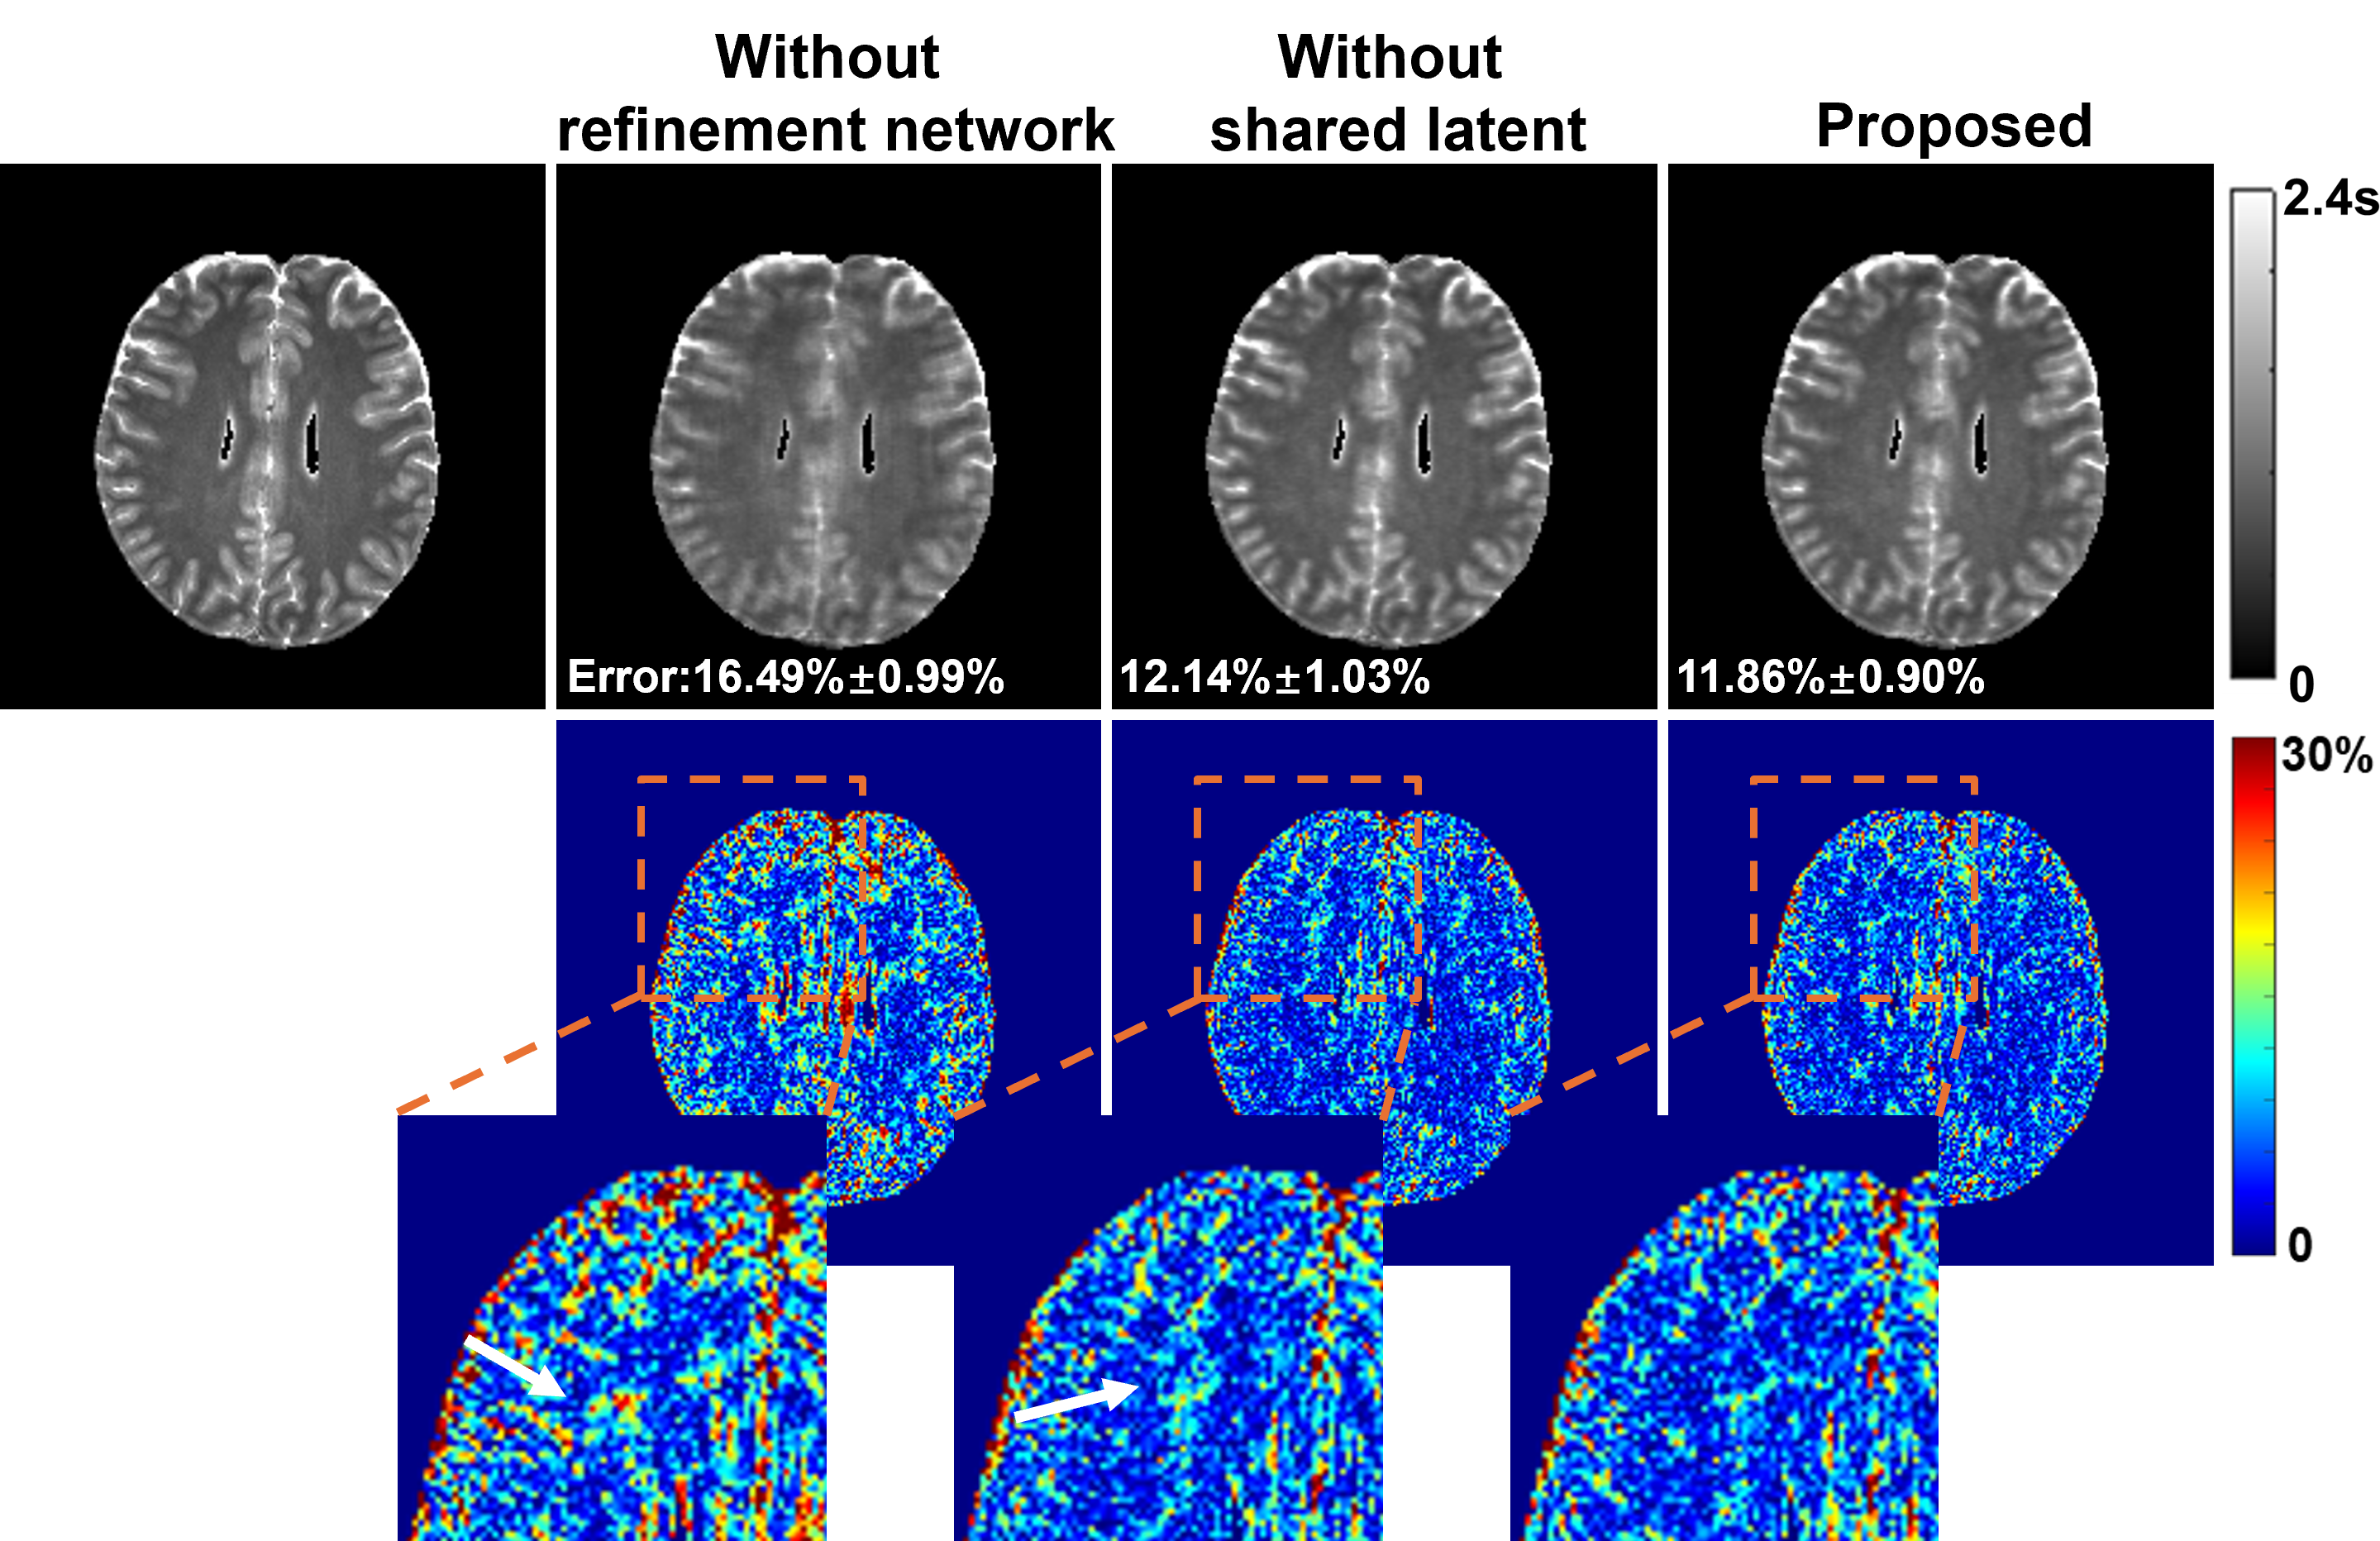

An Adaptive, Disentangled Representation Method for Multidimensional MRI Reconstruction

We present a new approach for representing and reconstructing multidimensional magnetic resonance imaging (MRI) data. Our method builds on a novel, learned feature-based image representation that disentangles different types of features, such as geometry and contrast, into distinct low-dimensional latent spaces, enabling better exploitation of feature correlations in multidimensional images and incorporation of pre-learned priors specific to different feature types for reconstruction. More specifically, the disentanglement was achieved via an encoderdecoder network and image transfer training using large public data, enhanced by a style-based decoder design. A latent diffusion model was introduced to impose stronger constraints on distinct feature spaces. New reconstruction formulations and algorithms were developed to integrate the learned representation with a zero-shot selfsupervised learning adaptation and subspace modeling. The proposed method has been evaluated on accelerated T1 and T2 parameter mapping, achieving improved performance over state-of-the-art reconstruction methods, without task-specific supervised training or fine-tuning. This work offers a new strategy for learning-based multidimensional image reconstruction where only limited data are available for problem-specific or task-specific training.

paper research